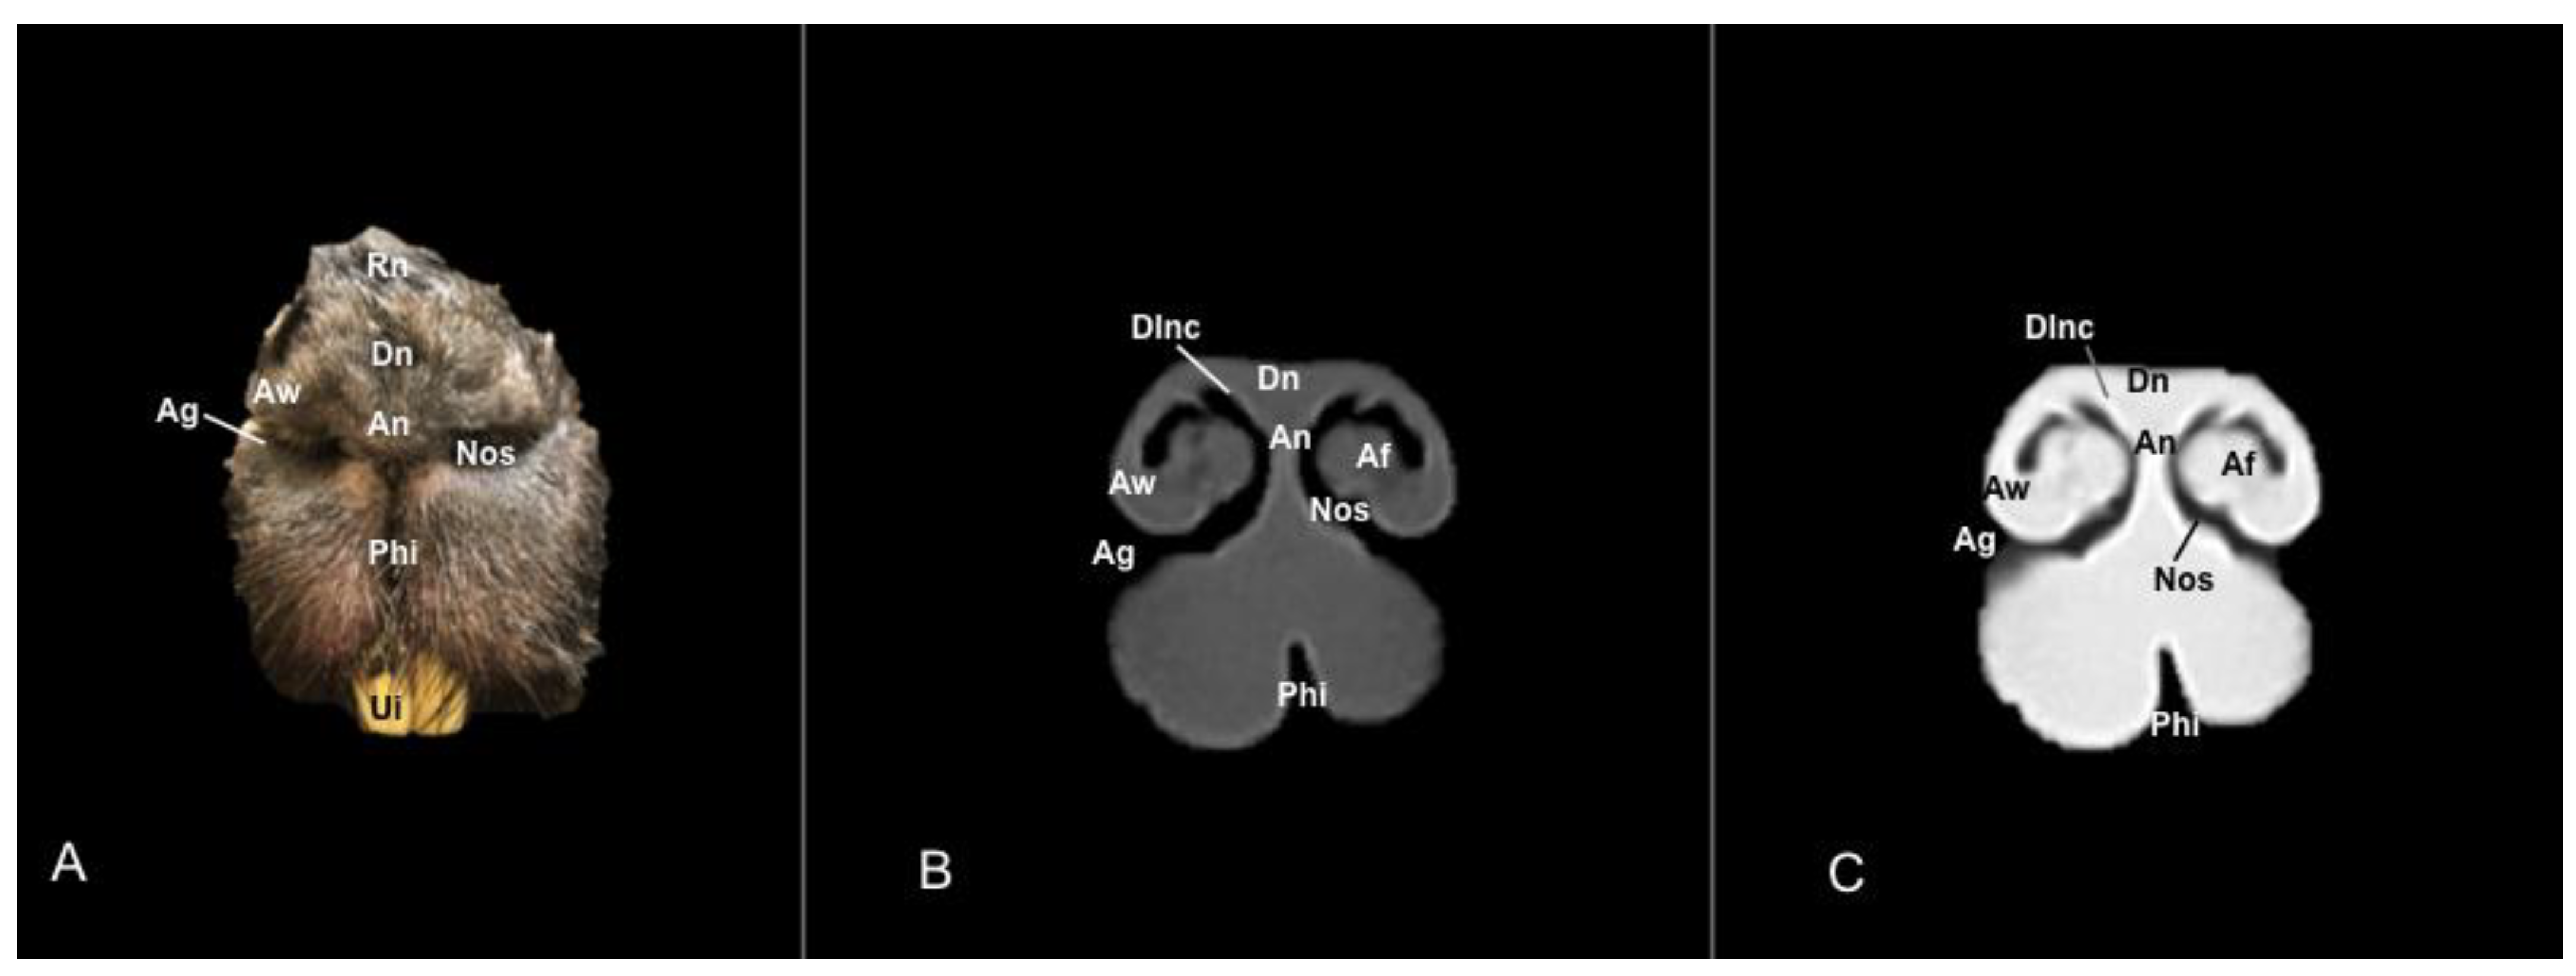

3.1. Anatomical Sections

3.2. Computed Tomography (CT)